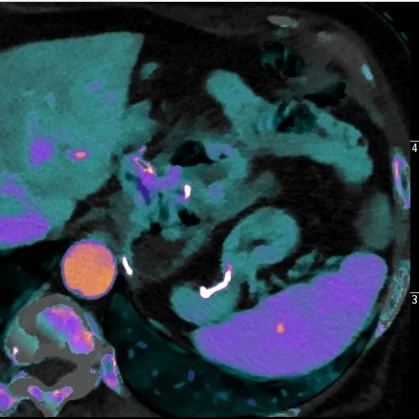

Iodine map: The wall discontinuity from the marginal ulcer (orange arrow) is obvious.

Iodine overlay shows finding well